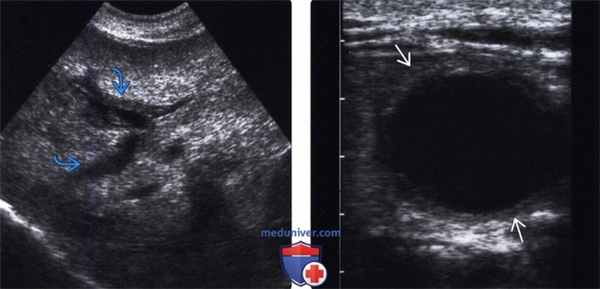

(Левый) На продольном УЗ срезе правой доли печени определяется расширение и утолщение стенки внутрипеченочного желчного протока.

(Правый) На поперечном УЗ срезе желчного пузыря определяется круговое утолщение его стенки, конкременты не визуализируются.